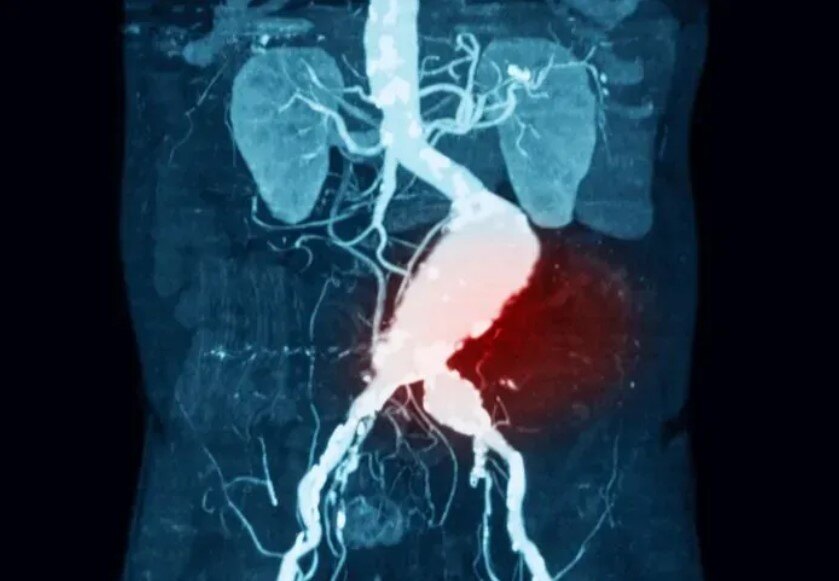

腹主動脈瘤破裂腹主動脈瘤(AAA)是身體最大的動脈——主動脈在腹部部分的擴張。隨著時間的推移,動脈瘤生長緩慢,小動脈瘤通常沒有任何癥狀。然而,較大的動脈瘤和迅速擴大的動脈瘤會引起癥狀,甚至破裂或夾層。AAA破裂和夾層是危及生命的情況,可引起嚴重的低血壓、頭暈、心率加快和突然的劇烈腹痛,如果不能識別和適當治療,將導致嚴重的發(fā)病率和死亡率,未經治療的死亡率接近100%。中間綠色部分為腹主動脈雖然許多AAA患者(腹主動脈直徑大于3cm)被確定為接受了搶先修復術,從而降低了死亡率,但多達50%的主動脈瘤患者的主要表現(xiàn)是動脈瘤破裂。破裂主動脈瘤患者的死亡率難以計算,但據(jù)國內外文獻報道,歷史上的急性死亡率高達90%,而采用當前外科手術方式的急性死亡率高達75%。AAA好發(fā)于65~85歲男性。這些動脈瘤在破裂前通常無癥狀,破裂是一種災難性的并發(fā)癥。導致動脈瘤擴張的原因有直接創(chuàng)傷、慢性感染、急性感染、炎癥等。動脈粥樣硬化性主動脈壁損傷被認為是AAA發(fā)生的主要危險因素,這種傳統(tǒng)觀點最近受到了挑戰(zhàn)。67歲男性,已知腹主動脈瘤,有腰背部和右側腹股溝疼痛3個月的病史。患者行腰椎及骨盆MRI檢查。MRI后立即獲得的連續(xù)軸位CT血管成像(CTA)顯示右側腹膜后大量血腫,并伴有造影劑從主動脈后外側外滲(箭頭)。手術中,看到右側腹膜后大量血腫,病理評估顯示主動脈壁不連續(xù)區(qū)域和相關的機化性血腫。當主動脈壁的機械應力超過壁組織的抗拉強度時,AAA破裂。雖然最初認為簡化的拉普拉斯定律(LawofLaplace)可以預測壁面應力,但實驗證據(jù)表明,壁應力的預測更加復雜,因為它受到動脈瘤位置、結構和腔內血栓的影響。TIPS:拉普拉斯定律是物理學和數(shù)學中的基本原理,它描述了充滿液體的容器內的壓力和容器壁的張力之間的關系。當考慮到動脈中形成的壓力時,它特別相關。簡單地說,拉普拉斯定律就是血管內的壓力與管壁的張力成正比,與血管的半徑成反比。在數(shù)學上,可以表示為:P=2T/r;其中P為壓力,T為張力,r為容器半徑。不同角度的VonMises壁應力輪廓圖,在收縮壓峰值時患者特定的腹主動脈瘤幾何形狀。中間的圖是截面圖。動脈瘤后壁存在高應力區(qū),而近端瘤頸處為壁應力峰值。腹主動脈瘤的大小和擴張速度是預測破裂的最重要因素AAA的大小和擴張速度是預測破裂的最重要因素。根據(jù)一般共識,較大動脈瘤患者應接受手術治療。較小動脈瘤的臨床治療方法存在爭議。對于4.0~5.5cm小動脈瘤的處理,目前臨床研究較少。結論表明,早期介入治療與動脈瘤直徑≥5.5cm時介入治療患者的生存率相似。米國退伍軍人管理局的一項研究表明,早期干預可降低手術并發(fā)癥。在快速擴張的動脈瘤中可以觀察到與初始大小無關的主動脈壁裂隙和破裂。多項研究也顯示,動脈瘤破裂家族史可使腹動脈瘤破裂的風險增加數(shù)倍。另外,與無破裂家族史的患者相比,有破裂家族史的患者發(fā)生動脈瘤破裂的年齡較早(65歲vs.75歲)。大多數(shù)AAA患者的動脈瘤直徑小于5.5cm。由于5.5~5.9cm動脈瘤的1年破裂發(fā)生率顯著增加至9.4%,因此這是手術修復風險低于破裂風險的通常閾值。此外,增加超過0.5cm的動脈瘤破裂風險增加,應及時修復。根據(jù)英國和米國的流行病學資料,大約4%~5%的猝死病例繼發(fā)于AAA破裂。只有約50%的AAA破裂患者到達醫(yī)院,破裂情況下的手術死亡率約為50%;然而,很難知道準確的數(shù)字。動脈瘤的易感因素已確定若干易感因素可增加動脈瘤形成的可能性。這些因素包括年齡較大、男性、收縮期和舒張期高血壓、當前或既往吸煙史以及一級親屬有AAA病史。男性50歲后和女性60歲后,接下來的每一個十年,動脈瘤的風險增加。男性患動脈瘤的可能性是女性的4倍,有一級親屬患AAA的風險增加4倍。吸煙是最重要的可糾正的危險因素,既影響患動脈瘤的可能性,也影響生長加速的速度。病史與體檢雖然理想情況下,患者應該在出現(xiàn)動脈瘤破裂等并發(fā)癥之前就被識別和治療,但超過一半的AAA破裂患者之前有未診斷的動脈瘤,多達30%的AAA破裂患者最初被誤診。據(jù)報道,25%~50%的AAA破裂患者表現(xiàn)為低血壓、腰背痛和搏動性腫塊的典型三聯(lián)征。破裂的可能表現(xiàn)包括原因不明的低血壓、腹股溝疼痛,有時下肢疼痛。其他可能的并發(fā)癥是血尿或消化道出血。因此,對于表現(xiàn)多樣的該病,醫(yī)師應高度懷疑該疾病,并降低評估閾值。在臨床表現(xiàn)上,休克程度因部位、大小和延遲表現(xiàn)而異。前外側壁的破裂直接與腹腔相連,所以通常導致當場死亡有關。后外側壁破裂與腹膜后間隙相通,因此病人通常存活。小破裂較大破裂失血量少,小破裂可初步封閉破裂于腹膜后,減少失血量。據(jù)報道,體格檢查發(fā)現(xiàn)搏動性腫塊的敏感性為51%~100%。研究表明,動脈瘤檢出的總靈敏度隨著動脈瘤大小的增加而增加,對3.0~3.9cm動脈瘤的靈敏度為29%,對4.0~4.9cm動脈瘤的靈敏度為50%,對>5.0cm動脈瘤的靈敏度為76%。肥胖已被證明會降低檢測的準確性。Grey-Turner征,即血液沿腹膜后剝離而累及脅部的瘀斑罕見,但在某些病例中可檢測到外側壁的堅實性。診斷與治療對于血流動力學不穩(wěn)定的患者,可僅根據(jù)癥狀(低血壓、腰背痛和腹部搏動性包塊)或通過床旁超聲確診后將患者送入手術室。對文獻的系統(tǒng)綜述顯示,超聲診斷的靈敏度為98%~100%,特異度為94%~100%。這些結果與在放射科病房進行的超聲篩查相似,后者報告的靈敏度為94%~100%,特異度為98%~100%。腹主動脈瘤(直徑7cm),超聲影像顯示動脈瘤真腔(左下方)與附壁血栓(右上方)主動脈夾層的超聲檢查。在血流動力學穩(wěn)定的患者中,鑒別AAA破裂的首選診斷研究是CT動脈成像(CTA),因為它提供了識別鄰近/受累腎動脈以及動脈瘤形態(tài)的能力。計算機斷層掃描血管造影(CTA)掃描的容積再現(xiàn),一些患者有疊加的動脈瘤節(jié)段。(a,b)患者在t1(左)和t2(右)出現(xiàn)不良演變的圖像。(c,d)患者在t1(左)和t2(右)時的圖像。對于到急診科就診的疑似AAA破裂患者,評估和處置的及時性至關重要,在疑似AAA破裂的病例中,早期與血管外科醫(yī)生會診,同時進行診斷性檢查,有助于促進最終處置到手術室。研究提示,術前液體復蘇策略(包括收縮壓為80~100mmHg的允許性低血壓)可能改善結局。然而,文獻中并沒有隨機對照試驗來證實這些發(fā)現(xiàn)。AAA破裂患者經常需要血液復蘇,往往需要大量輸血。研究表明,自體輸血的患者和較高濃度新鮮冷凍血漿[FFP]輸注的患者(壓積紅細胞[PRBC]:FFP=1:1)有改善的結局。如果不及時治療,AAA破裂在數(shù)小時至一周內幾乎都是致命的。實施開放修復術和血管內修復術的決策復雜,必須考慮患者因素,如年齡、患者合并癥和患者血流動力學狀態(tài)。動脈瘤因素,如位置、大小和形狀;外科醫(yī)生的經驗;以及可用的資源。雖然非隨機研究已經證明血管內修復術可改善發(fā)病率和死亡率,但當這些研究針對患者的血流動力學狀態(tài)進行控制時,這些益處尚未得到證實。此外,對于開放手術PK(比較)?血管內修復術的隨機對照試驗進行的薈萃分析表明,一種修復方法并不優(yōu)于另一種方法。腹主動脈瘤開放修復術腹主動脈瘤腔內修復術腹主動脈瘤腔內修復術前后的CTA影像